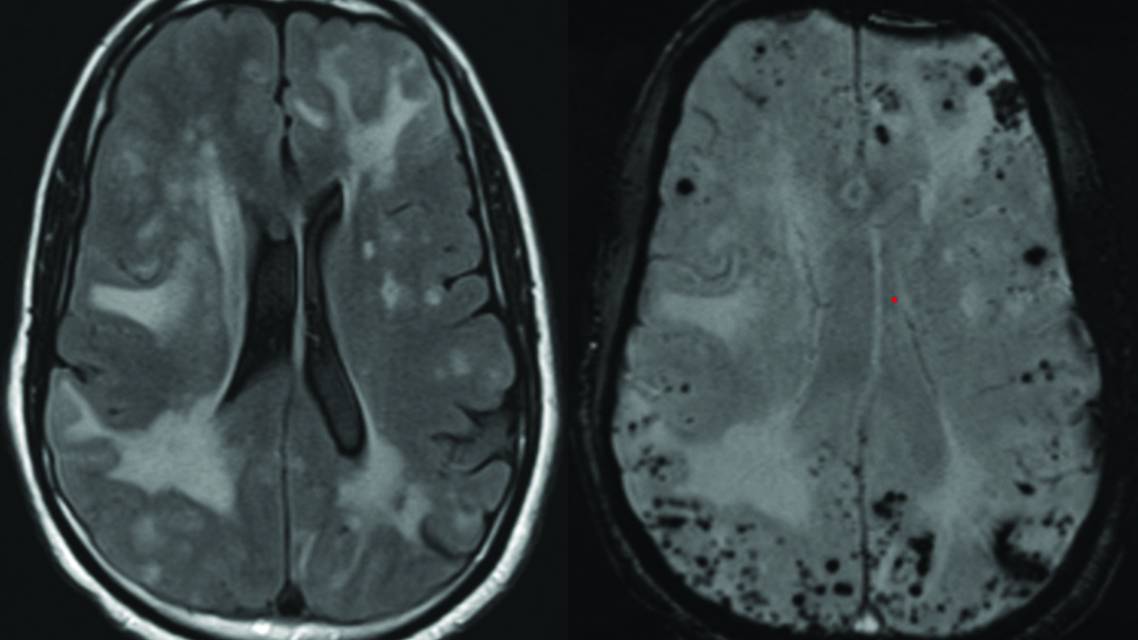

Figure 4. MRI brain images from an individual aged mid-70s with active cerebral amyloid angiopathy–related inflammation. Axial T2-weighted fluid-attenuated inversion recovery image shows diffuse pattern of vasogenic edema (A). Susceptibility-weighted imaging shows diffuse cerebral microbleeds in areas of asymmetric vasogenic edema meeting radiographic criteria for cerebral amyloid angiopathy–related inflammation (B).

Cerebral Amyloid Angiopathy–Related Inflammation

CAA-RI, which typically affects adult women with cerebral amyloid angiopathy in their sixth to seventh decade of life, is underrecognized and underdiagnosed.26 Clinical manifestations include headaches, subacute cognitive decline, seizures, and focal deficits. Inflammation is largely perivascular, driven by lymphocytes and microglia, without substantial vessel wall destruction.27 MRI shows asymmetric vasogenic edema with associated lobar microbleeds and occasionally superficial sulcal siderosis (Figure 4). Leptomeningeal enhancement and infarcts, when present, are usually mild. CSF tests show elevated protein levels in most individuals, and, less commonly, may reveal mild pleocytosis. A biopsy confirms perivascular T-cell–mediated inflammation around Aβ-laden vessels.25 Treatment of individuals with CAA-RI begins with corticosteroids; steroid-sparing agents (eg, cyclophosphamide, mycophenolate, azathioprine) are reserved for relapsing or high-risk cases. Monitoring patients with serial MRI scans and clinical assessment is essential. Early recognition and timely immunotherapy often lead to favorable outcomes.